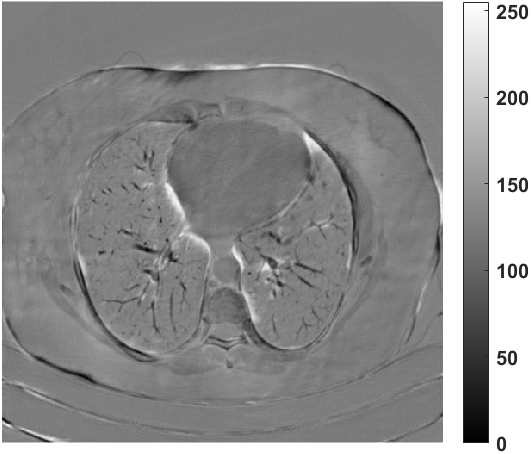

We further increase the noise level contained in the raw data to 10% white Gaussian noises and list the quantitative results in Table IV. It can be observed that the reconstruction performance of the TV model is poor in the case of high-level noises with PSNR dropping by 4 to 5 dB compared to the previous experiments. On the other hand, the performance of the learning-based methods is less sensitive to noises. The SIPID method relying on the sinogram interpolation works better than FBP-Unet. And the deep unrolling methods (i.e., PD-net, IFSR-net, SFSR-net) outperform the traditional iterative algorithm when the scanning range is limited and data is corrupted by noises. Similar to the previous experiments, compared with other deep learning algorithms, our LRIP-nets give the reconstruction results with higher PSNR and SSIM. Moreover, the low-resolution image obtained by the projection data down-sampled with rate 1/8 always gives the best reconstruction results with more than 2 dB PSNR and 0.05 SSIM increments compared to the PD-net. Fig. 6 illustrates the reconstructed images from different methodologies with scanning angular range of and 10% Gaussian noises. It can be seen that the both TV model and the FBP-Unet suffers from significant artifacts, which present distortions in the angular range of the missing scan. Other learning-based methods provides better visual qualities than FBP-Unet, and our LRIP-net1/8 still gives the best reconstruction result with correct boundaries and fine structures.

Fig. 7 manifests the reconstruction results of these methods with scanning angular of . It can be seen that both FBP and FBP-Unet produce serious artifacts within the range of missing angles. The TV model performs well in removing Poisson noises, but it can not handle the artifacts very well. Similarly, there left obvious artifacts on boundaries and different degrees of missing in visceral tissues of the reconstruction images obtained by the SIPID, PD-net and FSR-net. The visceral tissue and boundaries of our LRIP-net reconstructions are more intact and smoother, especially for the LRIP-net1/8 which gives the ideal boundaries. The observation becomes even apparent if we look at the zoom-in regions, where the LRIP-nets can produce results with fine structures. Therefore, we conclude that the low-resolution image prior can effectively improve the qualities of the limited-angle CT reconstruction.